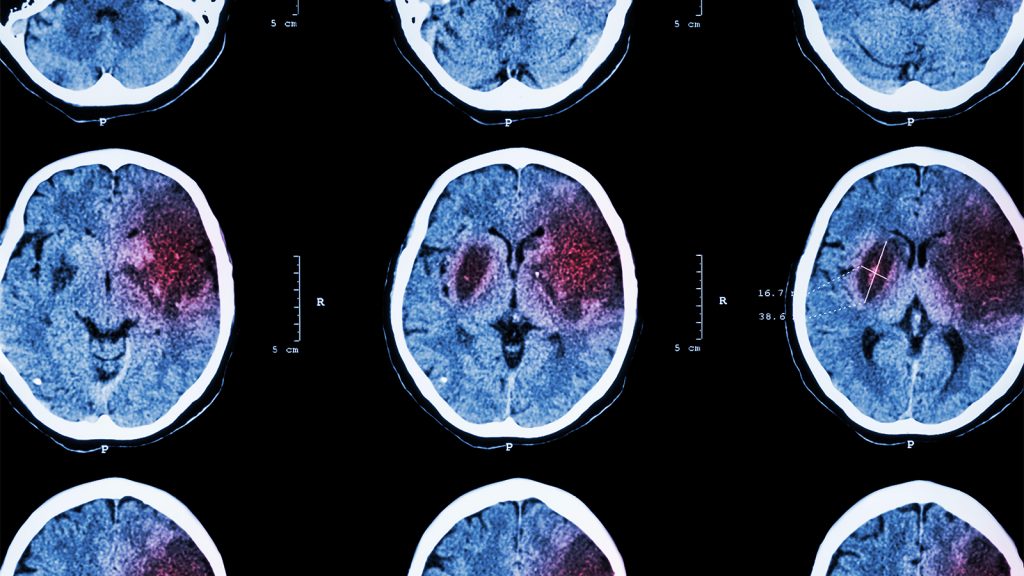

Stroke Risk Is Changing With the Climate

(MedPage Today) — The world endured its hottest summer on record in 2024, and the transition to fall brought devastation from multiple hurricanes in the U.S. The growing effects of climate change are widespread and becoming more severe. Now, new…